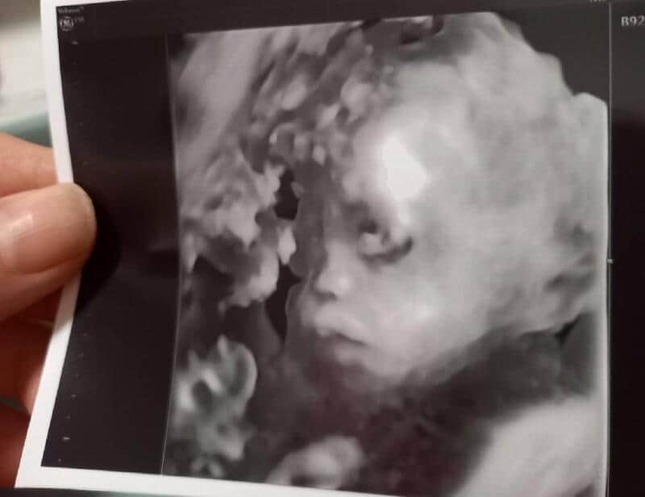

• すっかり赤ちゃんの顔!

すっかり赤ちゃんの顔!